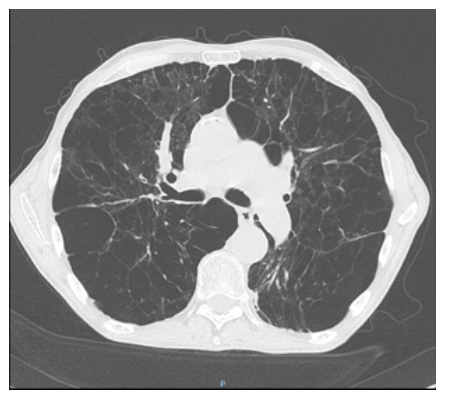

Le patient retourne à domicile. Il est suivi par un pneumologue qui le revoit à 6 mois de son hospitalisation. Il reste très symptomatique malgré le traitement de fond par bronchodilatateur de longue durée d’action seul bien conduit et la réhabilitation respiratoire. Il se plaint beaucoup d’un encombrement bronchique avec bronchorrhée. Il n’a pas refait d’exacerbation ces 6 derniers mois. Entre-temps il a vu un cardiologue qui lui a prescrit un bêtabloquant cardio-sélectif. Le pneumologue lui prescrit un scanner qui est le suivant.

Figure 5.

BPCO précoce ( 45 ans) avec emphysème majeur.

Il s’agit ici d’un emphysème bulleux typique : zones d’hypodensité traduisant une raréfaction du parenchyme pulmonaire. On parle de bulle quand les zones d’hypodensité sont cerclées par une paroi fine et ont un diamètre de plus de 1 cm.

Un déficit en alpha-1 antitrypsine est à suspecter devant :

– un emphysème majeur prédominant ;

– une BPCO précoce (< 45 ans) ;

– une BPCO chez un patient non ou peu tabagique ;

– des antécédents familiaux.

Il s’agit de la seule prédisposition génétique de la BPCO connue jusqu’à présent. Il est important de faire le diagnostic pour la descendance et car il est possible d’envisager une supplémentation en alpha-1 antitrypsine.